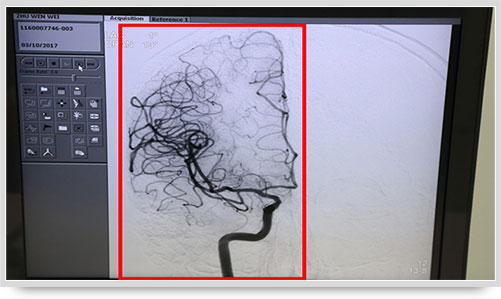

弓上造影、超选到颈内动脉、椎动脉......在数字减影技术下,注入显影剂后,导管经患者右侧股动脉在体内推进,由于股动脉离脑血管距离较远,中间“路程复杂”,对施术医生的要求非常之高。

同时,手术台前的液晶显示仪屏幕上清晰地现显出导管的路径,在李主任的操作下准确到达指定检查部位,各条血管的“庐山真面目”清晰可见。